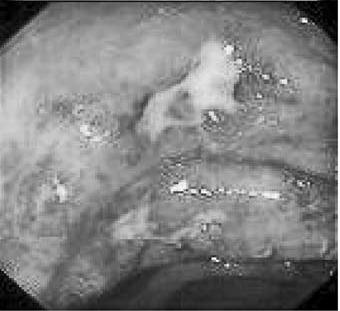

Рентгенологическая диагностика болезни Крона основывается на выявлении прерывистого характера поражения кишечника, вовлечения в процесс тонкой и толстой кишок, правосторонней локализации процесса в ободочной кишке с образованием глубоких язв‑трещин, внутренних свищей, ретроперитонеальных абсцессов с формированием свищей и слепых синусов в случаях вовлечения в процесс тонкой кишки. Ведущим рентгенологическим симптомом болезни Крона является сужение пораженного участка кишки. Степень сужения прямо пропорциональна давности заболевания. В отдельных случаях кишка суживается неравномерно и эксцентрично. Гаустры в недалеко зашедших случаях сглаживаются и принимают неправильную форму, при прогрессировании процесса они исчезают вовсе. Весьма характерным при болезни Крона считается чередование пораженных фрагментов кишки с нормальными. Эндоскопическая картина при болезни Крона характеризуется наличием афтоидных язв на фоне неизмененной слизистой оболочки. По мере прогрессирования процесса язвы увеличиваются в размерах, принимают линейную форму. Чередование островков сохранившейся слизистой оболочки с глубокими продольными и поперечными язвами‑трещинами создает картину «булыжной мостовой» (рис. 177).

Рис. 177. Эндоскопическая картина при болезни Крона.